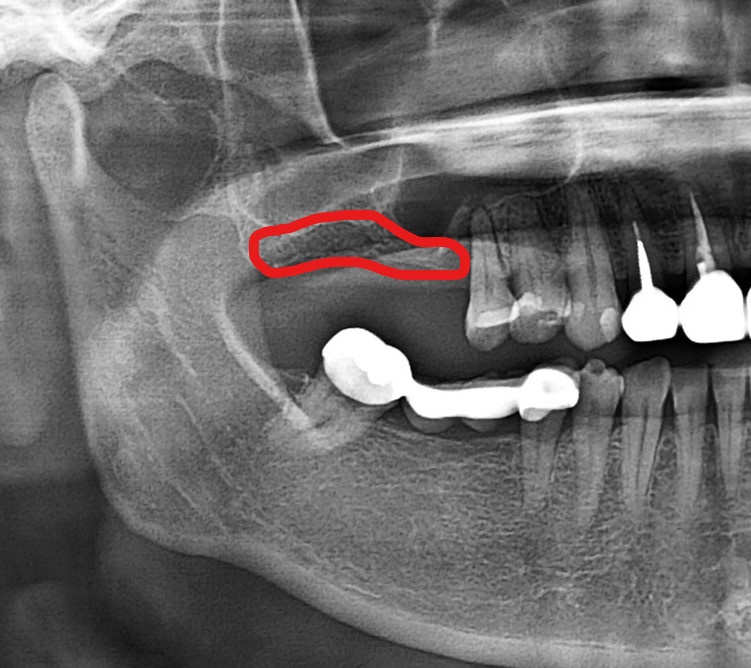

- 術 前

患者因長期缺牙以及鼻竇位置較低導致原先的骨量較薄較少,影響植牙的條件。